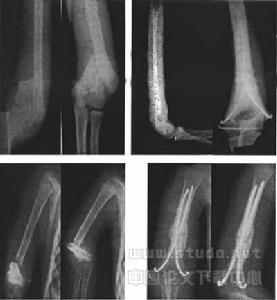

臨床主要根據骨折部位和損傷程度分為A、B、C三型。A型:關節外骨折;髁上骨折(又分為伸直型、屈曲型、粉碎型)多見於10歲以下小兒;外上髁骨折,很少見;內上髁撕脫性骨折,較多見。B型:關節內單髁骨折;外髁骨折包括外上髁和肱骨小頭,較多見;肱骨小頭骨折,少見;內髁骨折,包括以內上髁和滑車;滑車骨折,少見而處理困難。C型:髁間粉碎性骨折,成人多見。輕者,為“T”型或“Y”型骨折;重者,支離破碎,四分五裂,處理難度大。

(1)適應症:①合併血管神經損傷者;②軟組織嵌入骨折間隙;③閉合復位失敗者;④外固定難以穩定復位者;⑤畸形癒合,明顯影響功能和外觀者。(2)手術固定方式的選擇;①內上髁折:兩根細克氏針或細松質骨拉力螺釘;②外髁骨折、內髁骨折:兩顆松質骨拉力螺釘或兩顆克氏細針或可吸收螺釘;③髁上骨折:交叉克氏針,欠穩定需輔以外固定;或1/3管狀鋼板或重建鋼板均可;④肱骨小頭或滑車骨折:兩根細松質骨螺釘由關節面向上穿;⑤C型骨折:“T”型或“Y”型骨折,(A)空心螺釘固定內外髁,1/3管狀鋼板固定髁與乾;(B)人字塑形鋼板;(C)交叉長螺釘或克氏針加外固定。碎塊多的C型骨折,需要多種固定材料,可分四步行術,①克氏針固定內外髁;②以克氏針為導針鑽入一4mm空心松質骨拉力螺釘,再鑽入一3.5mm全螺紋空心螺釘加強固定內外髁;③內側用一5~7孔的1/3管狀鋼板,外側用一5~7孔重建鋼板固定髁與乾。④可吸收螺釘固定關節面小碎片。缺損較多者應植松質骨。(3)手術中及術後注意要點;①鷹嘴窩的小碎片宜清除,避免影響伸肘;②外側入路應注意橈神經,內側或後側入路應游離尺神經,以免損傷;③外髁骨折復位時不可將伸肌腱完全剝離,術中常需伸肌腱來定位骨折面;④如內固定不可靠需輔以外固定四周以上者,可考慮切除鷹嘴尖5mm,有利於伸肘。